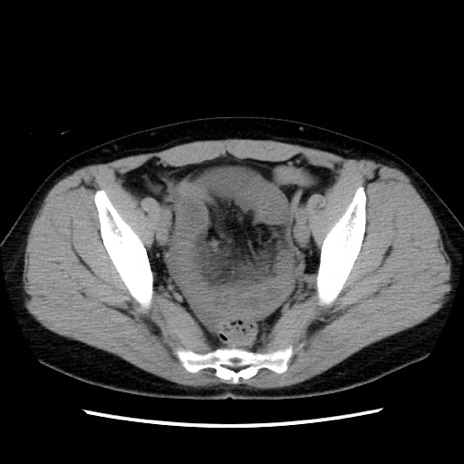

症例10(横断像)

【症例】 50歳代女性

【主訴】 腹痛

【現病歴】前日生レバーを食べた。今朝に排便あり。 昼前に突然発症の腹痛を生じ、当院救急外来を受診した。

【既往歴】 子宮筋腫にてで子宮全摘後

【身体所見】 意識清明、腹部:平坦、軟、下腹部やや左を中心に圧痛・反跳痛あり、筋性防御あり

【データ】WBC 7800、CRP 0.07